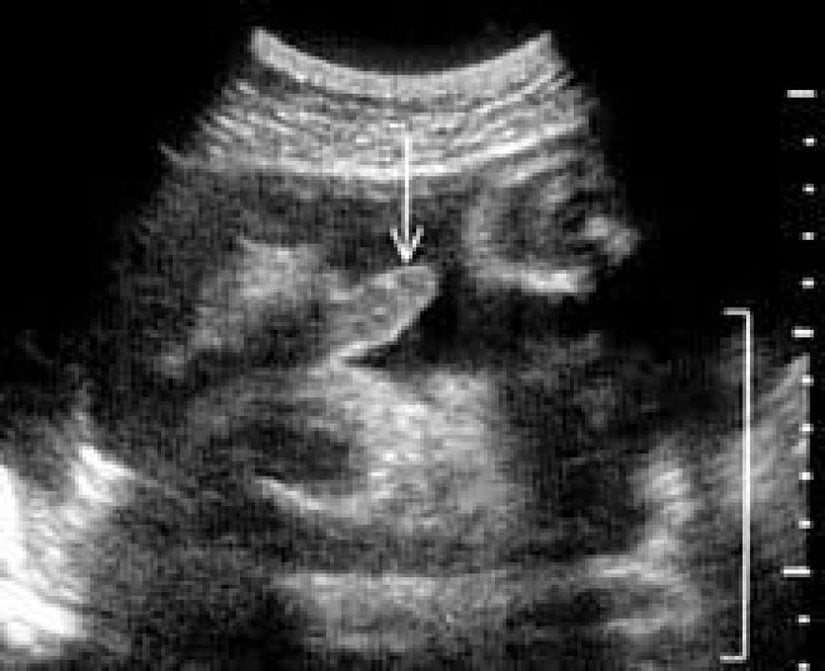

Evet, erkek bebeklerin annelerinin karnında ilk ereksiyonlarını yaşadıkları bilinmektedir. Öyle ki, erkek bebekler ana rahminde her saat birden fazla defa erekte olabilirler. Bunun tam olarak neden gerçekleştiği bilinmemektedir, çünkü erkekler normalde ergenlik çağına kadar pek fazla erekte olmazlar. Aşağıdaki fotoğrafta 36 haftalık bir bebeğin ereksiyonu görülmektedir.